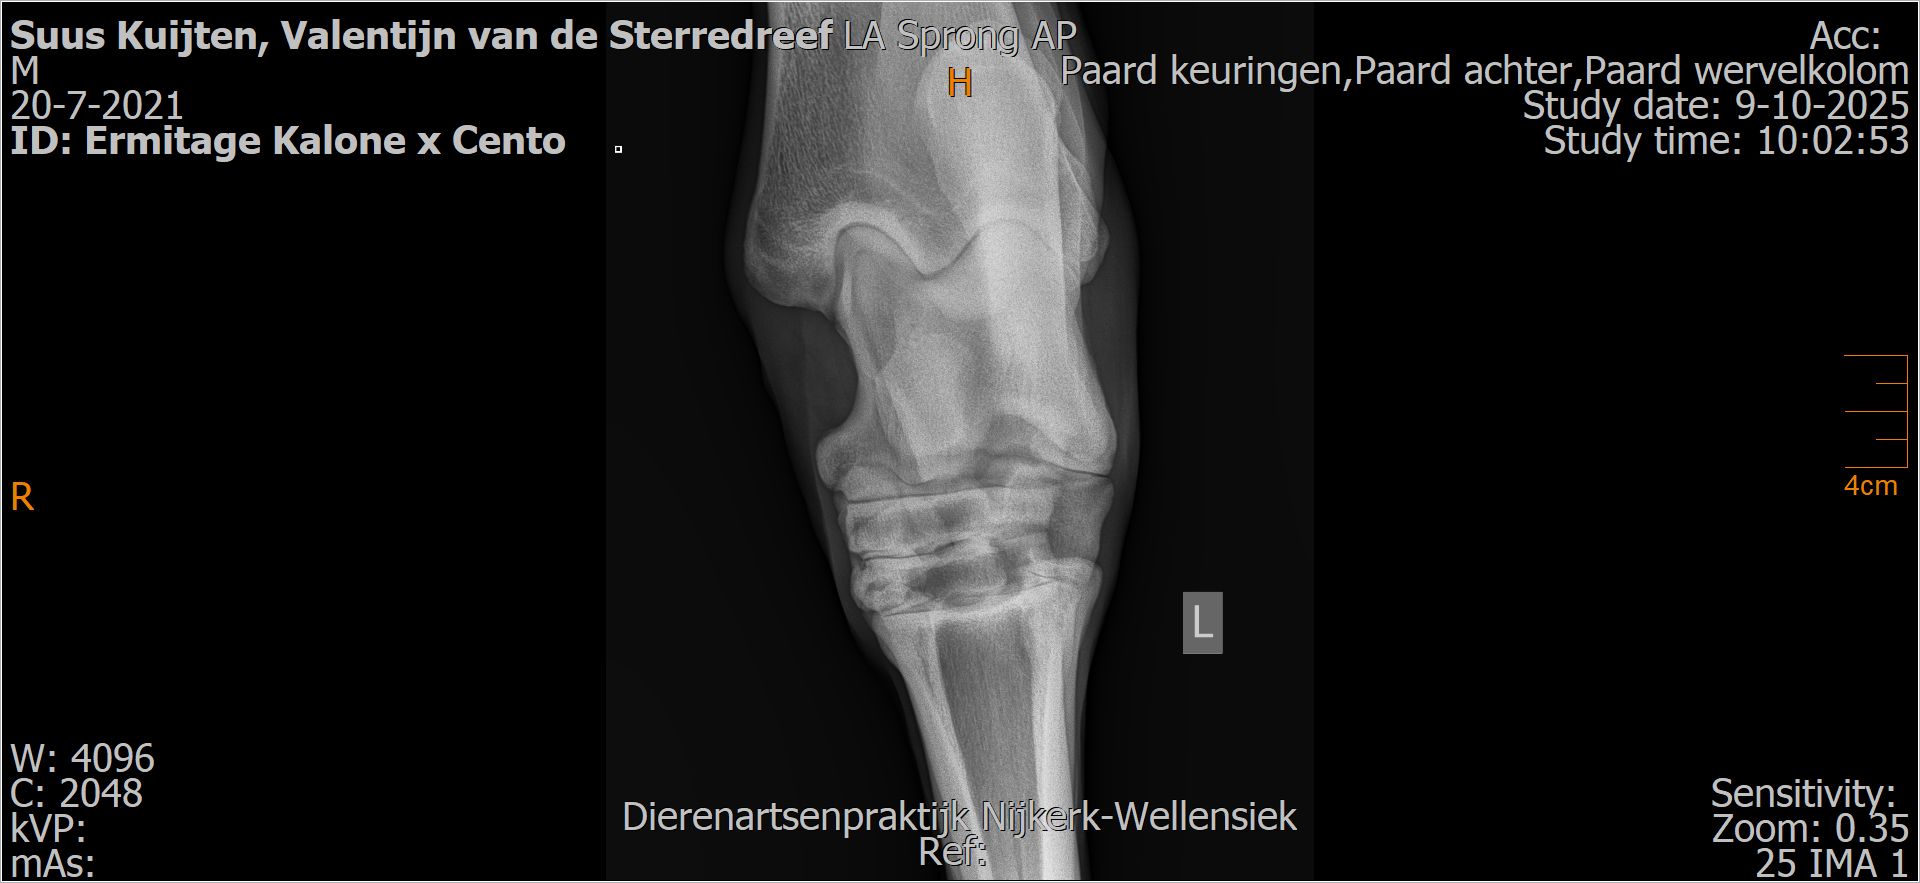

Valentijn van de Sterredreef

Leeftijd:

4

Röntgenfoto’s